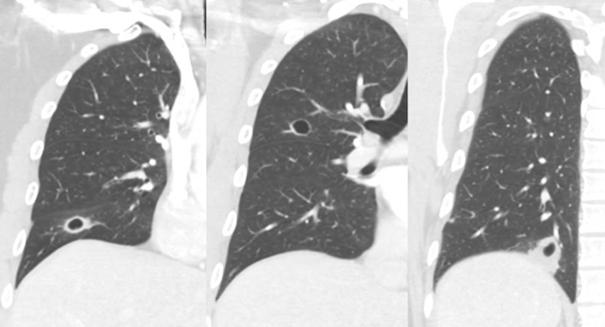

Evaluación del ADN circulante tumoral en cáncer de mama

Este informe profundiza en el uso del ADN tumoral circulante para monitorear el cáncer de mama, explorando cómo pueden revelar detalles sobre la evolución del tumor, la respuestaaltratamientoylapresenciadeenfermedadmínimaresidual.

El ADN circulante tumoral (ADNct) evalúa componentes celulares de las neoplasias a través del

plasma. El cáncer de mama (CM) es la neoplasia más frecuente y el estudio del ADNct permite obtener información de la neoplasia de forma mínimamente invasiva.LospacientesconCMenennivelesmásaltosde ADNct que los sujetos sin diagnósco de cáncer La detecciónylosnivelesaltosdeADNctsonmásfrecuentes en los pacientes con enfermedad metastásica con mayor volumen tumoral y con enfermedad agresiva, como el fenopo triple negavo y HER2+ El ADNct permite seleccionar el tratamiento dirigido adecuado en la enfermedad metastásica. En el CM temprano, la eliminación del ADNct durante la quimioterapia neoadyuvante se ha asociado con tasas más altas de respuesta patológica completa y una sobrevida prolongada; además, predice la recaída con varios meses deantelación.